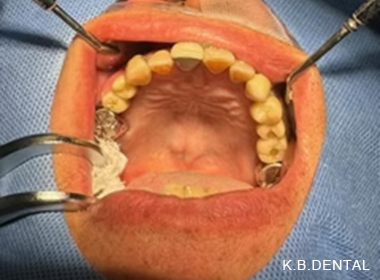

口蓋隆起(こうがいりゅうき)

口蓋隆起 症例1

噛む力の強い方に起きやすいケースです。上顎の総入れ歯が入れられないということで来院されました。なぜこのように上顎の骨が出てくるかというと、例えば、家の屋根があったとして、上から力がかかると応力で屋根の真ん中がたわんできます。

それと同じように正中口蓋の真ん中に亀裂(ヒビ)が入らないように、人間の体も生体防御反応で守ろうとし、真ん中に骨を作ろうとして骨添加が起きます。トレーニングでベンチプレスをする方でも、最初は腕が細い人がプルプル震えると思います。繰り返すうちに、だんだんと腕の骨の周囲を筋肉が肥大して腕を支えてくれます。それと同じような現象です。

口蓋隆起 症例2

口蓋隆起 症例3

歯の内側に発生したタイプの骨隆起です。静脈麻酔で約1時間半程度要します。